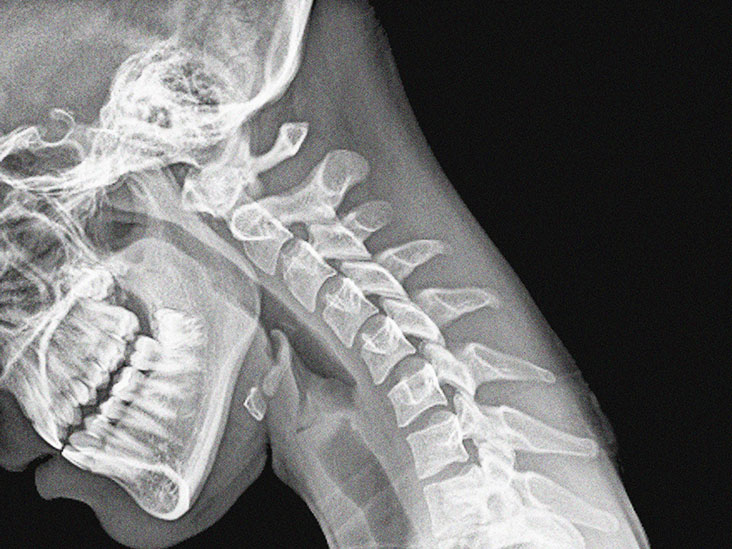

La detección de bandas oligoclonales del LCR implica someterse a un procedimiento llamado punción lumbar. Un médico insertará una aguja a través de la piel y dentro de la columna. Antes de la prueba, un médico puede ordenar pruebas de imágenes, como una tomografía computarizada o una resonancia magnética, para garantizar que la persona se someta al procedimiento de manera segura.

El procedimiento puede variar según las prácticas del médico y el estado de salud de la persona. Algunos médicos pueden realizar una punción lumbar utilizando imágenes médicas como guía, como una ecografía o una radiología intervencionista.